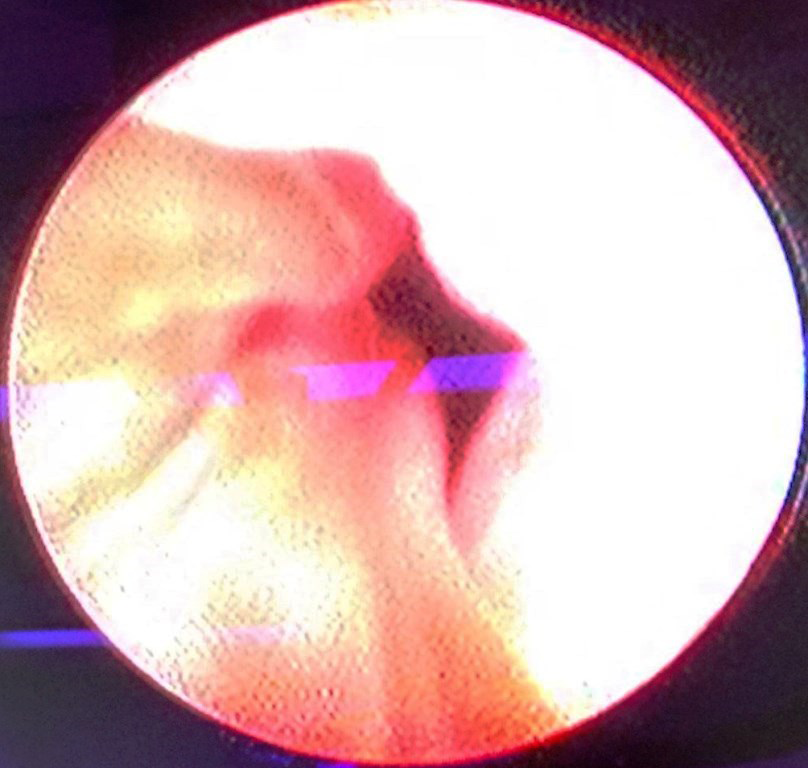

A six months old female patient, presented in the emergency department with a red fleshy actively bleeding introtial mass. She was resuscitated and required blood and fresh frozen plasma transfusions. Systemic examination revealed microcephaly, bilateral genu valgus deformity, local examination revealed, a 5 cms x 3 cms reddish partly gangrenous mass prolapsing through the urethra, the uretheral meatus was completely occluded with it and vaginal orifice was normal (Figure 1). Routine biochemical tests (Kidney Function Test) were normal; there was no evidence of coagulation abnormalities or urinary tract infection. Patent foramen ovale was detected on echocardiography. Ultrasonogram of the KUB region showed mild hydroureteronephrosis on the right side, urinary bladder was normal. Cystouretheroscopy showed the pedunculated mass to be arising in the region of trigone towards right side, right ureteric orifice could not be located, left ureteric orifice was normal and urinary bladder showed no other abnormality (Figure 2). A single prolapsed mass was resected cystoscopically, haemostasis achieved and no 8 Fr Foley’s catheter was left indwelling for 2 days. Histopathology revealed tumor was composed of dilated vascular channels lined with endothelial cells suggesting cavernous haemangioma. She had an uneventful post-operative course, and the hydroureteronephrosis resolved on follow up.

Figure 2 Cystoscopy Picture Demonstarting Pedical of Haemangioma In Urethra (Block arrow- Pedicle, line- bladder lumen).